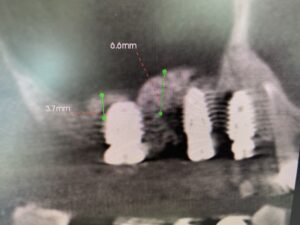

術前CT画像に示すよう、残存骨の高さは僅かしかないので、造骨の為にソケットリフトを併用しなければなりません。

更に5.6番の間には、膜を挙げ易くする為にベント、スリット等の工夫を設置、内圧減少の役割も考えます。